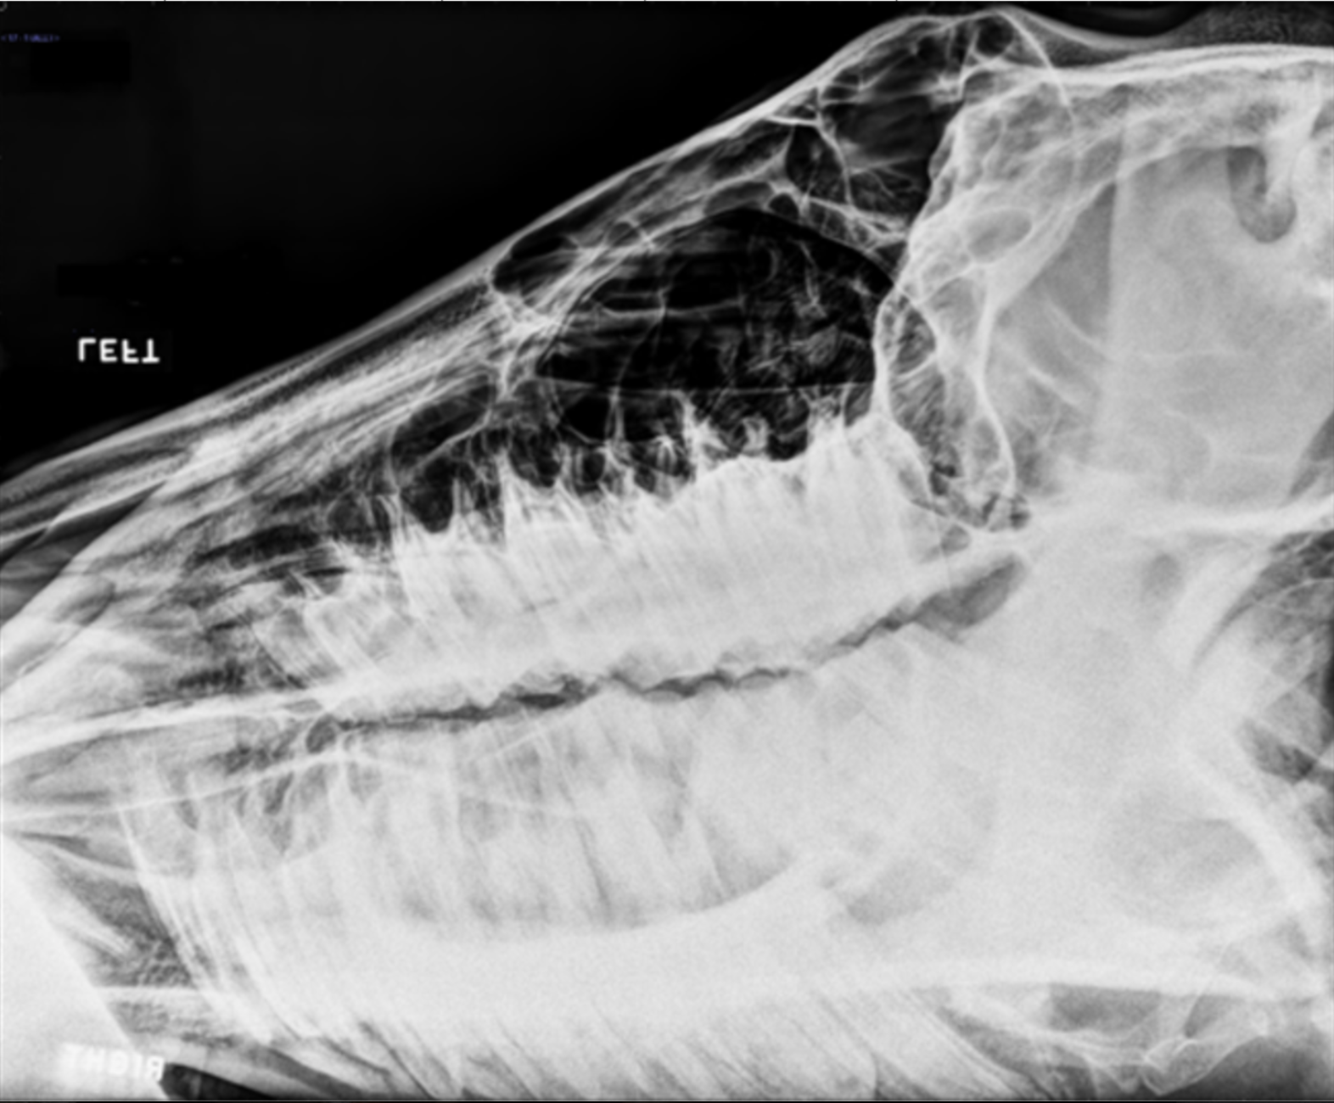

left lateral equine skull

orange: gutteral pouches (left and right)

yellow: pharynx

blue: ethmotrubinates

red: mandibles (left and right)

white: epiglottis

dark blue: styelohyoid bones (left and right)

green: basiphenoid